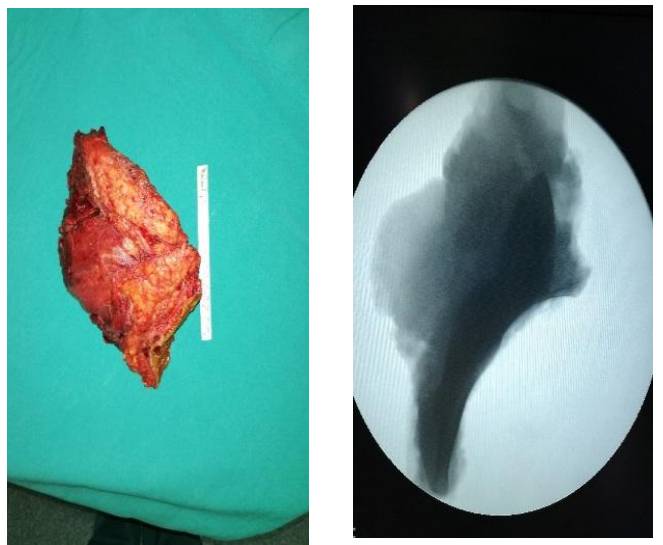

Ameliyat Esnası: Rezeksiyon ve rekonstrüksiyon uygulanımı görülmekte

Ameliyat Esnası: Çıkarılan rezeksiyon dokusunun klinik ve radyolojik görüntüsü